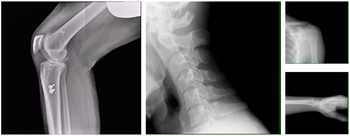

例如,关节置换病人不宜搬动,可在床旁进行动态影像检查,若膝骨关节炎达到重度而无法搬移到检查室,此时就可方便地将移动动态DR推到床旁,用动态影像评估关节活动度。在病人无法站立,甚至无法行CT检查时,移动动态DR提供为数不多的床旁关节运动功能影像和评估,方便医生设计后续治疗方案。